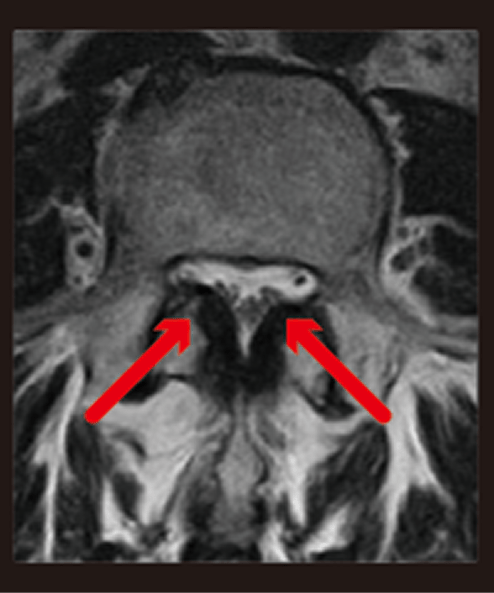

神経の通る管である脊柱管が、変形した骨や分厚くなったじん帯に圧迫されて狭くなっています(赤矢印)。

腰椎で発症すると、腰から下のしびれや痛みが出現します。

歩くとしびれや痛みが悪化し、休むとやわらぐを繰り返す、間欠性跛行(かんけつせいはこう)という症状が特徴的です。

椎間板(黒い部分)が脊柱管に突出しています(赤矢印)。

頸椎(首)と腰椎(腰)によく発生し、痛みやしびれなどの症状が出ます。